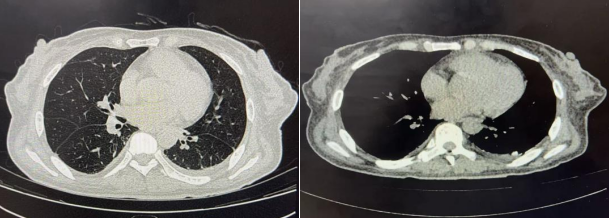

西安市第三医院胸外科近期收治的一名来自青海的患者,经既往术后患者介绍前来就诊。该患者在当地确诊后,经西安市第三医院多学科团队(胸外科、肾脏内科、麻醉科)联合评估,顺利接受手术治疗。术中通过胸腔镜可清晰观察到气体自膈肌薄弱处溢出,经胸壁小切口成功完成膈肌修补与胸膜固定。术后次日患者即恢复腹膜透析。